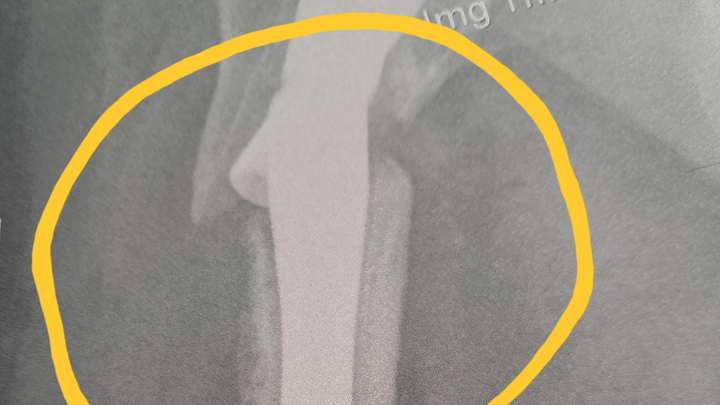

I am currently in the Dominican Republic and have suffered a catastrophic injury involving a broken hip and femur, resulting in my leg being effectively detached from the hip due to non-union. This is my third major femur-related injury in the past 14 months.

In November 2024, I suffered a serious fall in my home that resulted in a femur fracture requiring surgical intervention and the insertion of an intramedullary rod. After months of recovery, the rod re-fractured six months later while I was in the Dominican Republic, requiring a second surgery to remove and replace the hardware.

Unfortunately, due to undiagnosed osteoporosis, my bones failed to heal properly. I have now suffered a third and most severe injury: a broken hip and femur with hardware failure and non-union. I have been advised that I require an urgent total hip replacement and complex reconstructive surgery in order to walk again and to prevent further life-threatening complications.